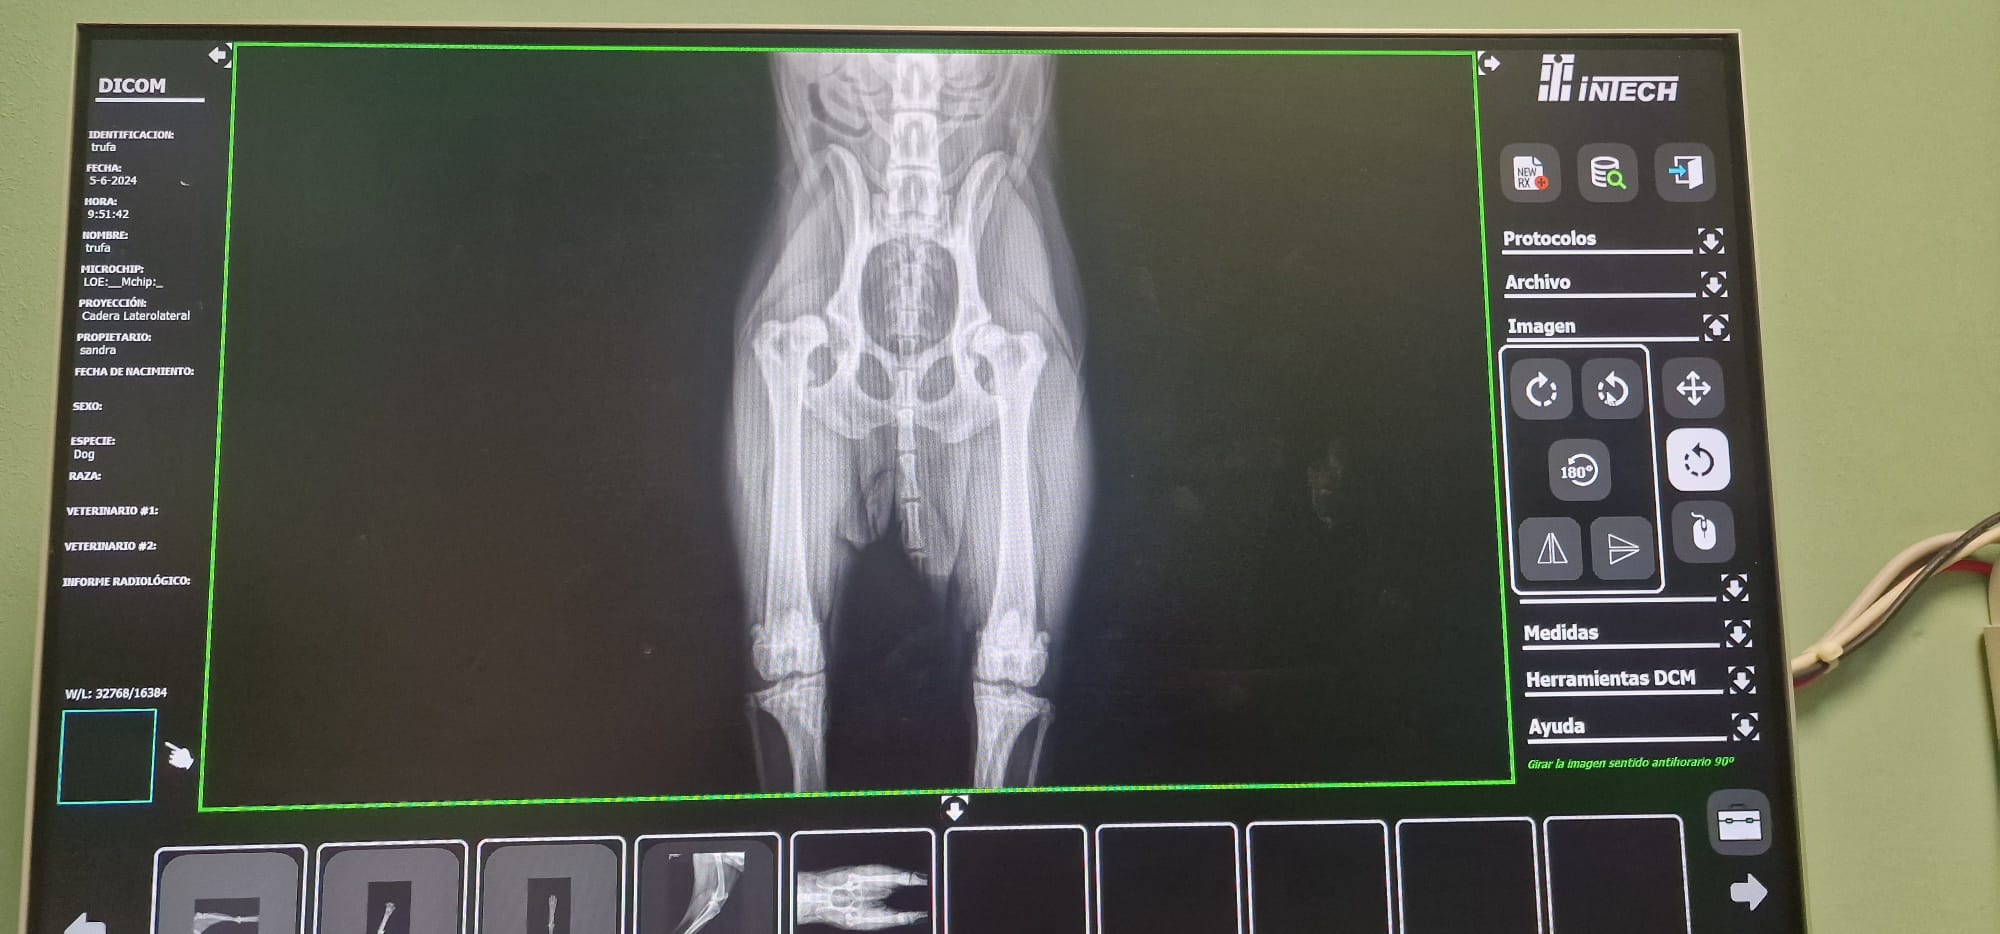

Radiografías = Salud en Imágenes 🐾🩺En Smile Vet, ofrecemos servicios de radiografías para cuidar la salud de tu mascota con precisión y cariño.

• Diagnóstico Rápido: Las radiografías nos permiten detectar problemas (óseos, dentales, respiratorios, cardiacos, etc.) y cuerpos extraños sin procedimientos invasivos. 🐶🐱

• Tecnología Avanzada: Utilizamos equipos modernos para obtener imágenes claras y detalladas, asegurando un diagnóstico eficaz.

• Cuidado Integral: Nuestro equipo interpreta los resultados para ofrecerte el mejor plan de tratamiento, siempre con el bienestar de tu mascota como prioridad. 🐾